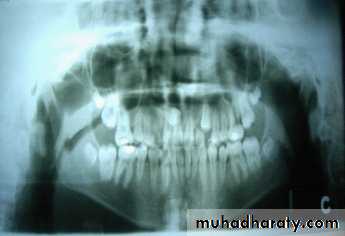

impaction

Position of canine root apex anteroposteriorly

Vertical canine crown height